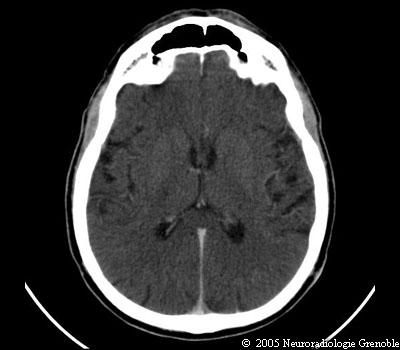

Radioanatomie TDM de l'encéphale

TDM cérébrale sans injection